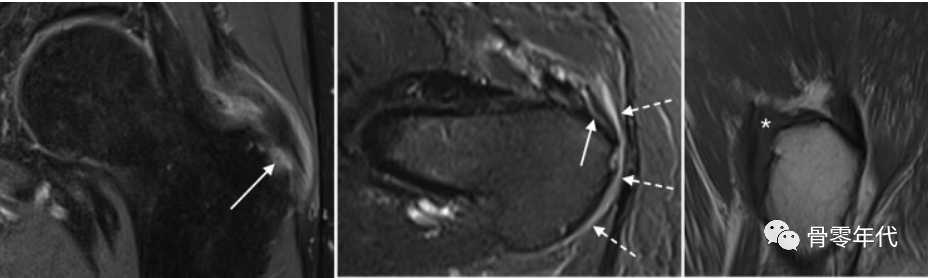

(a)一位74岁女性的右侧髋关节侧位X线片显示臀小肌腱附着处有一个大的突起(星号)。(b)重度臀小肌腱病(白色箭头),在矢状面T1加权像上插入末端(星号):仅有轻微的臀中肌腱病(黑色箭头),伴有微小的末端隆起。(c)轴位T1加权图像显示臀小肌严重脂肪变性,最明显的是后部和中部(白色箭头)。